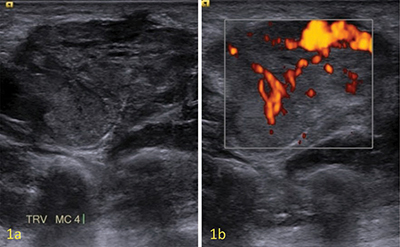

教学要点:血管网状肌瘤在磁共振成像上的表现为外周 T1 和 T2 高密度边缘、邻近的迂曲血管结构和暗网状征象。

Teaching point: Angioleiomyoma is defined on MR by a peripheral T1- and T2-hypointense rim, adjacent tortuous vascular structures, and a dark reticular sign.